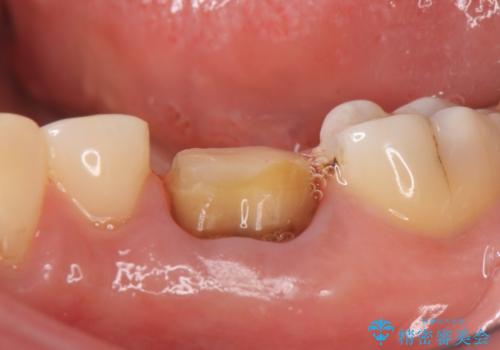

- 他院にて左下6の再根管治療を勧められ当院にいらっしゃった方の症例です。

再根管治療終了後、オールセラミッククラウンにて補綴を行いました。